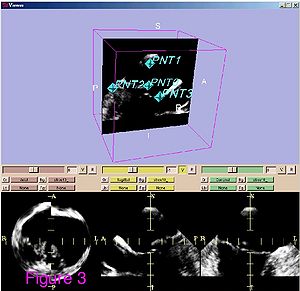

Publication: World Neurosurg. 2015 Dec 27. PMID: 26732948

Institution: Department of Neurosurgery, People's Liberation Army General Hospital, Beijing, China. Background/Purpose: OBJECTIVE: To investigate the feasibility and reliability of virtual endoscopy (VE) as a rapid, low-cost and interactive tool for suprasellar arachnoid cysts (SACs) diagnosis and surgical planning. Methods: 18 SACs patients treated with endoscopic ventriculocystostomy were recruited, and same number of endoscopic third ventriculostomy treated patients was randomly selected as VE reconstruction control group. After loading their DICOM data into free software 3D Slicer, VE reconstruction was independently performed by 3 blinded clinicians and the time required for each reconstruction was recorded. Other 3 blinded senior neurosurgeons interactively graded the visibility of VE by watching video recordings of endoscopic procedures. Based on the visibility scores, Receiver Operating Characteristic (ROC) curve analysis was used to investigate the reliability of VE to diagnose SACs, and the Bland-Altman plot was employed to assess the VE's reliability for surgical planning. In addition, intra-class correlation coefficient (ICC) was calculated to estimate the consistency among the results of 3 reconstructing performers. Results: All 3 independent reconstructing performers successfully completed VE simulation for all cases, and the average reconstructing time was 10.2±9.7 minutes. The area under ROC curve of cyst's visibility score was 0.96, implying its diagnostic value of SACs. Bland-Altman plot indicated good agreement between VE and intraoperative viewings, suggesting the VE's anatomical accuracy for surgical planning. In addition, ICC was 0.81, which revealed excellent inter-performer consistency of our simulation method. Conclusion: This study substantiated the feasibility and reliability of VE as a rapid, low-cost and interactive modality for SACs diagnosis and surgical planning. |